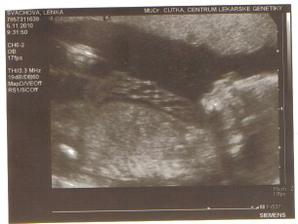

5.listopadu: absolvovali jsme UTZ na specializovaném genetickém pracovišti a ode dneška víme, že čekáme KLUKA 😀 😀 😀